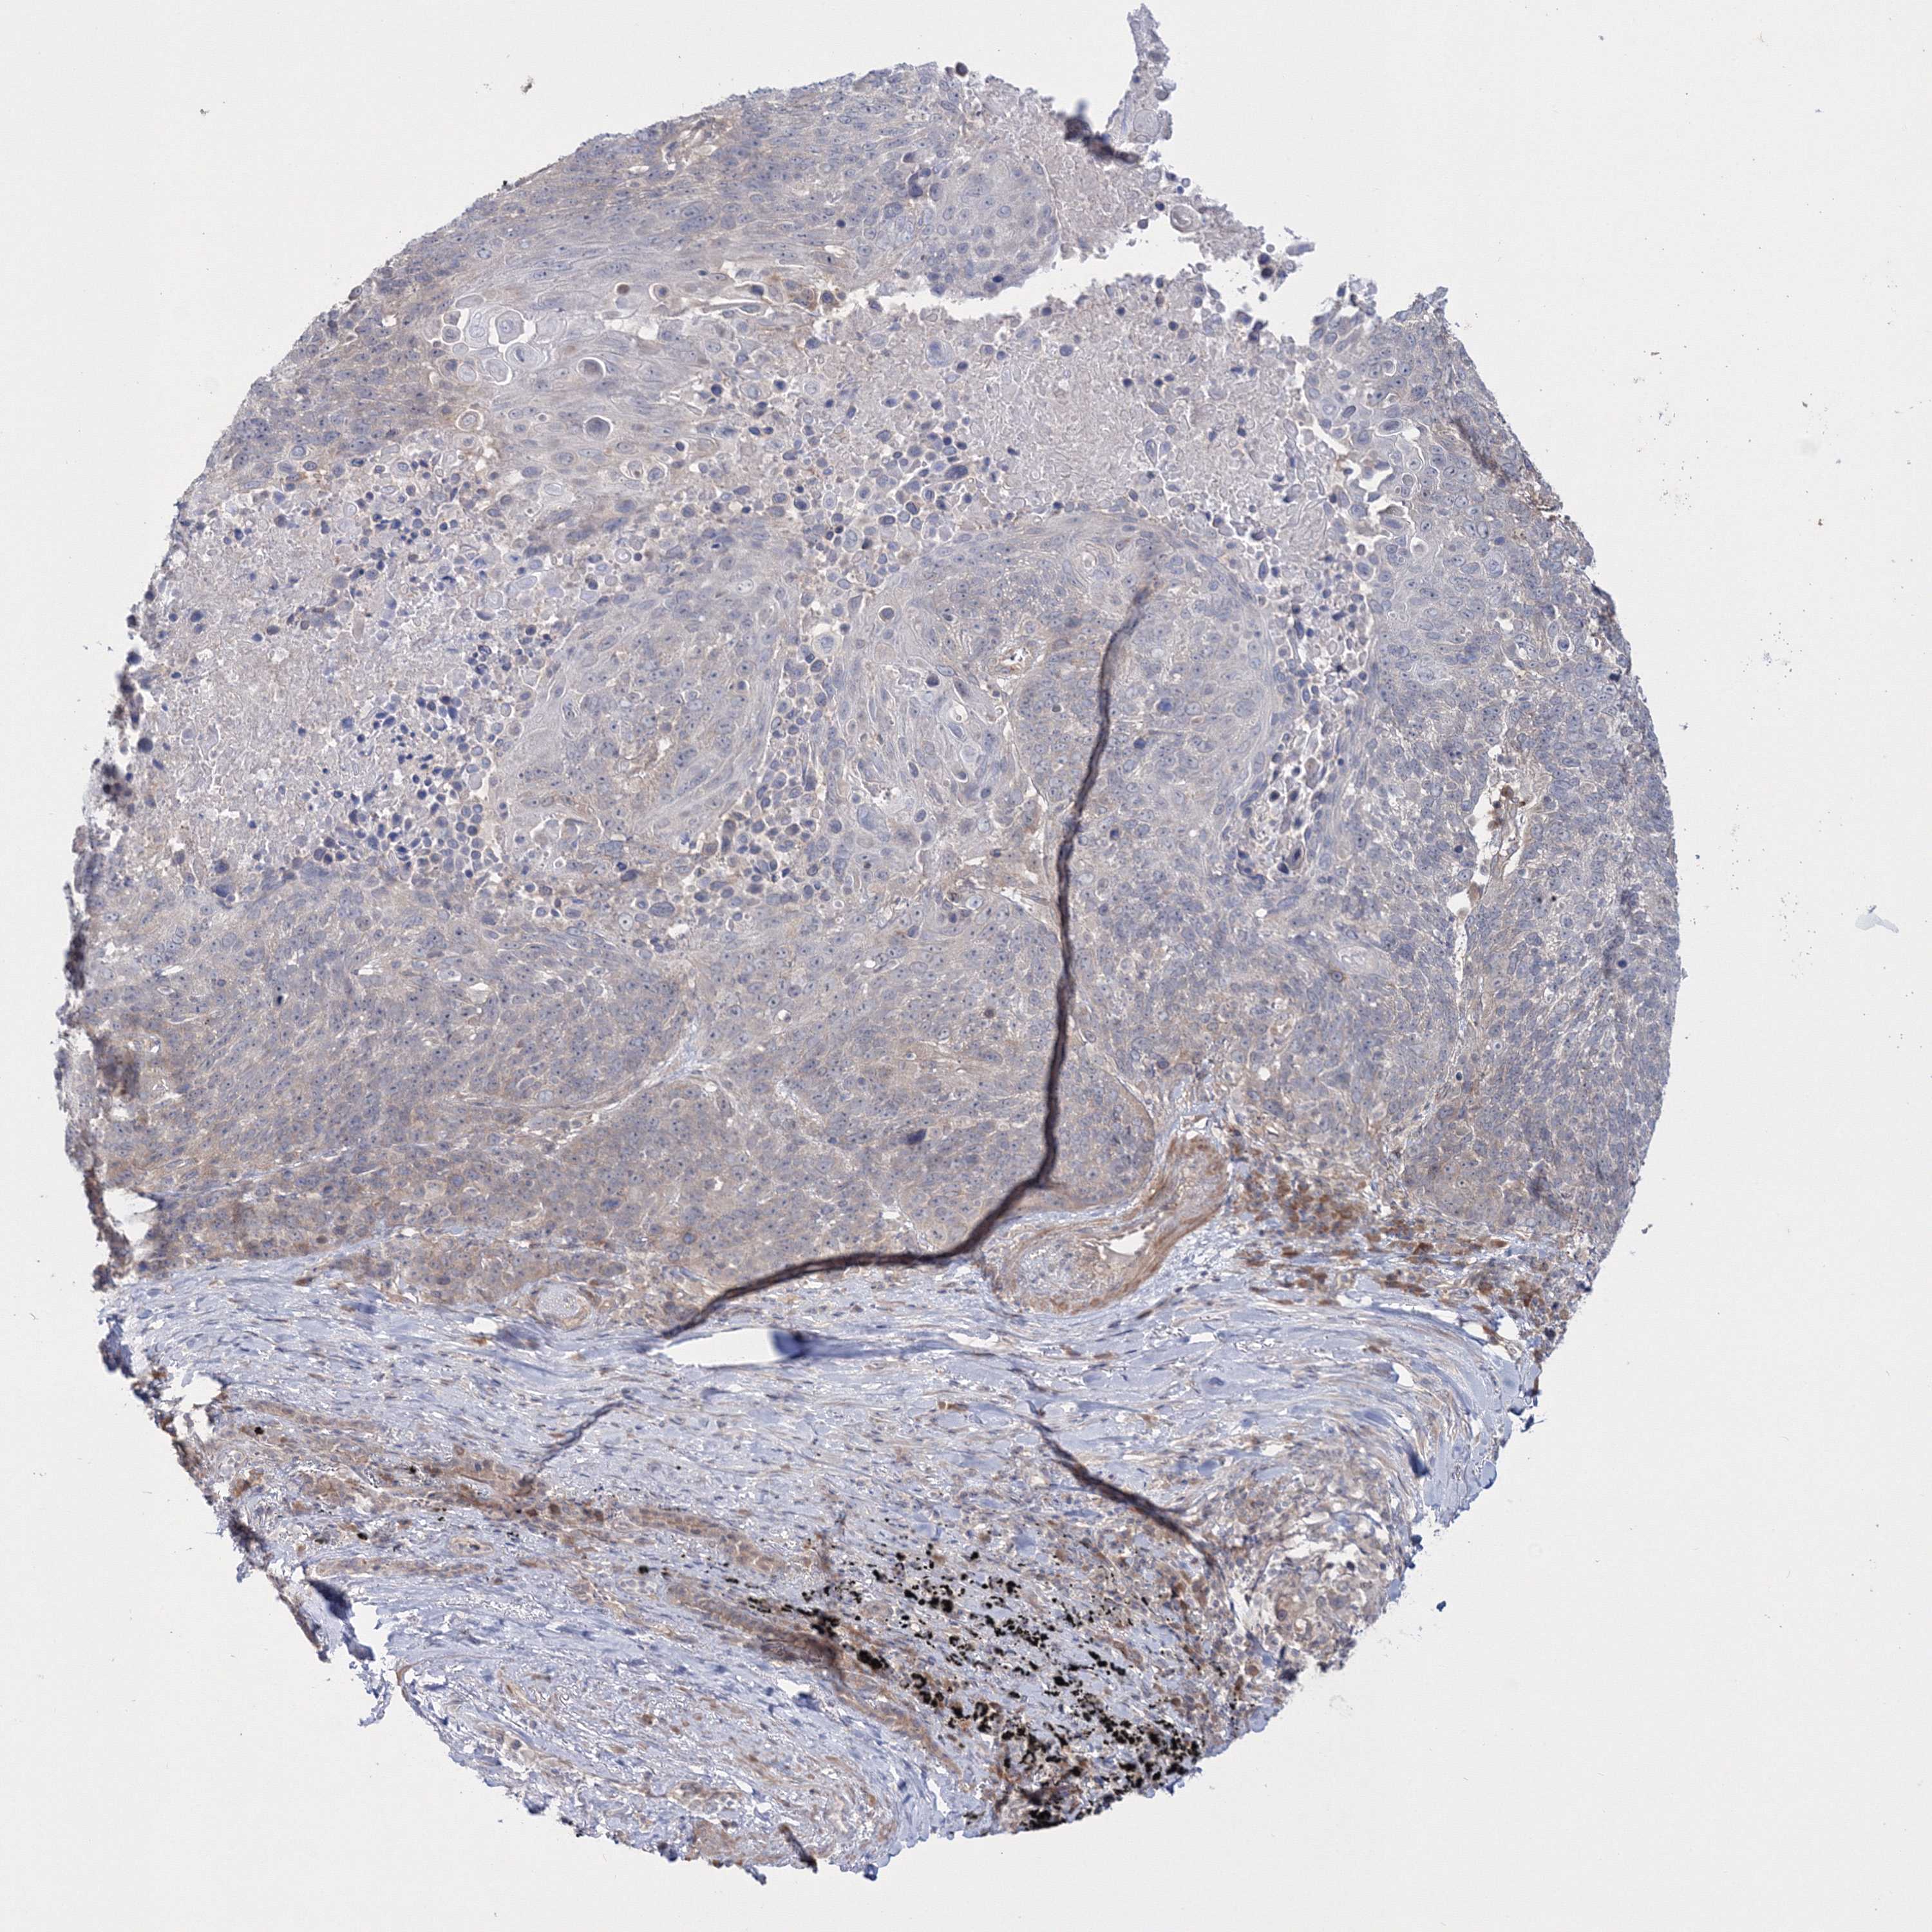

LUNG ADENOCARCINOMA (VALIDATION) - Interactive survival scatter ploti

The Survival Scatter plot shows the clinical status (i.e. dead or alive) for all individuals in the patient cohort, based on the same data that underlies the corresponding Kaplan-Meier plots. Patients that are alive at last time for follow-up are shown in blue and patients who have died during the study are shown in red.

The x-axis shows the expression levels (FPKM) of the investigated gene in the tumor tissue at the time of diagnosis. The y-axis shows the follow-up time after diagnosis (years). Both axes are complimented with kernel density curves demonstrating the data density over the axes. The top density plot shows the expression levels (FPKM) distribution among dead (red) and alive patients (blue). The right density plot shows the data density of the survived years of dead patients with high and low expression levels respectively, stratified using the cutoff indicated by the vertical dashed line through the Survival Scatter plot. This cutoff is automatically defined based on the FPKM cutoff that minimizes the p-score. The cutoff can be changed by dragging the vertical line or by entering a cutoff value in the square labeled "Current cut-off".

Under the Survival Scatter plot the p-score landscape (black curve; left axis) is shown together with dead median separation (red curve; right axis). Dead median separation is the difference in median mRNA expression between patients who have died with high and low expression, respectively. It is calculated as follows: median FPKM expression of dead patients with high expression - median FPKM expression of dead patients with low expression. This is intended to aid the user in visually exploring custom cutoffs and the associated p-scores and dead median separation.

Individual patient data is displayed and can be filtered by clicking on one or more of the category buttons on the top of the page. Categories describing expression level and patient information include: high, low, alive, dead, female, male and tumor stages. The scale of the x-axis can be toggled between linear and log-scale by clicking on the "x log" button. Mouse-over function shows TCGA ID, patient information and mRNA expression (FPKM) for each patient.

& Survival analysisi

Kaplan-Meier plots summarize results from analysis of correlation between mRNA expression level and patient survival. Patients were divided based on level of expression into one of the two groups "low" (under cut off) or "high" (over cut off). X-axis shows time for survival (years) and y-axis shows the probability of survival, where 1.0 corresponds to 100 percent.

IPMK is not prognostic in Lung Adenocarcinoma (validation)

: 6.2